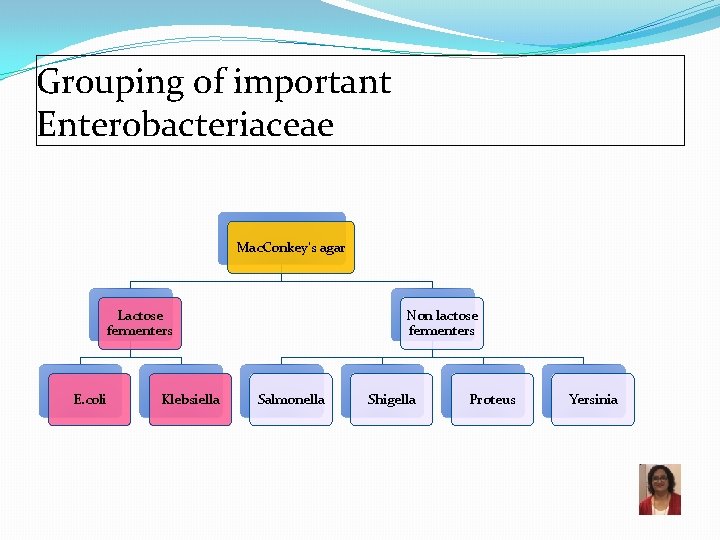

Grouping of important Enterobacteriaceae Mac. Conkey’s agar Lactose fermenters E. coli Klebsiella Non lactose fermenters Salmonella Shigella Proteus Yersinia